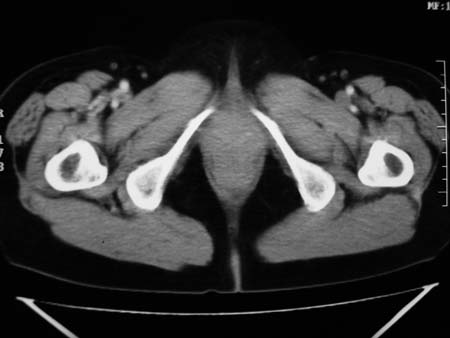

以下是引用卜一在2008-1-2 20:39:00的发言:[br]右侧附件区囊实性肿块,与膀胱壁分界不清,增强后实性部分显示强化。考虑为:右侧卵巢囊腺癌可能性大。支持!

以下是引用zhengfaming在2008-1-2 19:28:00的发言:[br]右下腹腔内附件区可见一囊实性混合密度块影,先考虑囊腺癌